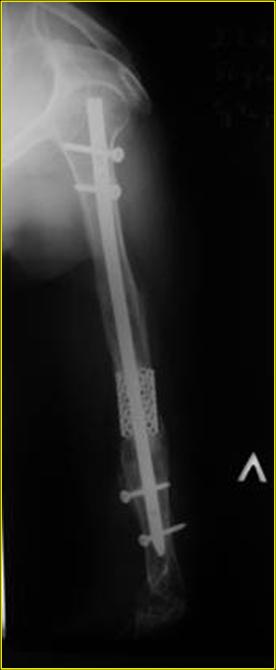

Типичная положительная ситуация для интрамедуллярного остеосинтеза с

использованием опорного металлокаркаса для компенсации дефекта.

Послеоперационное ведение активное или агрессивно-активное. Каркасы

можно заказать в МАТИ.

Рентгеновская версия реконструкции. хронология:

после операции, 2 мес. после операции, через 1 год

Движения в полном объеме восстановлены к 2 мес. после операции. Если надо могу показать мультик. Сейчас уже прошло более 3 лет, больная не

показывается. Успехов ЛАФ.